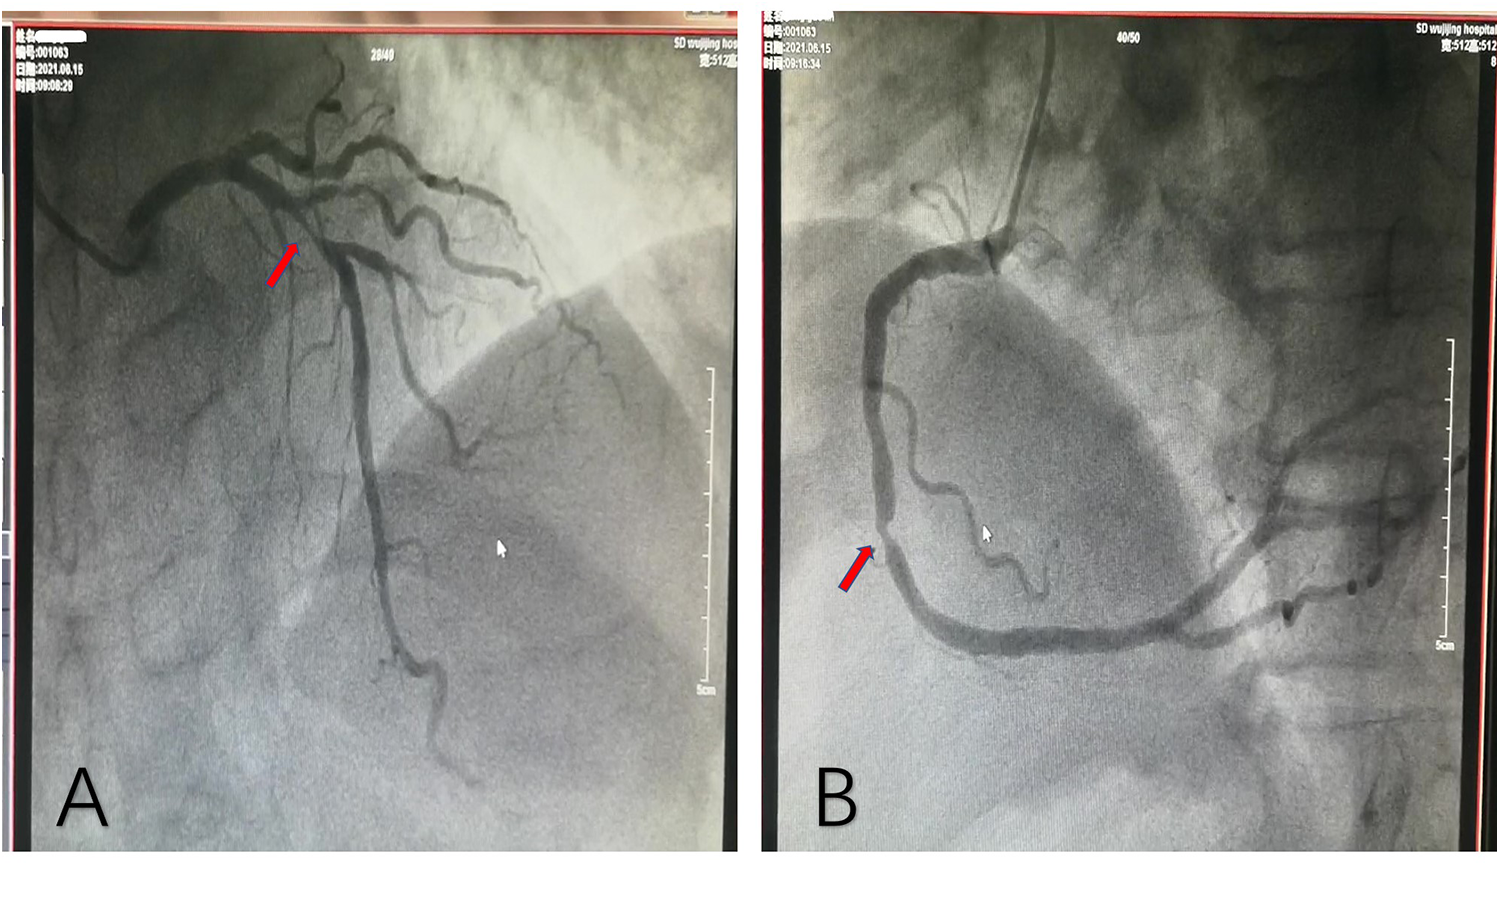

The patient, a 77-year-old man, was admitted due to “sudden unstable chest pain.” Resting for 15–20 min could alleviate the patient's chest tightness in the 2 months before admission. Half an hour before admission, the patient experienced chest tightness again during physical activity and was admitted to the emergency department with chest tightness lasting for 40 min. This patient had a history of hypertension for more than 10 years and oral administration of 80 mg valsartan and 5 mg amlodipine tablets daily has controlled his blood pressure (BP) to normal. The patient has a smoking history of 50 years, accompanied by 10 cigarettes per day, and his mother has a history of cerebral hemorrhage. Upon admission, physical examination showed a BP of 154/75 mmHg and heart rate of 68 beats/min; no significant abnormalities were observed during cardiopulmonary auscultation. There was no edema in both lower limbs. An ECG examination immediately upon admission showed sinus rhythm and ST-T changes, and the patient was preliminarily diagnosed with acute coronary syndrome (ACS). The patient refused a coronary intervention examination and received dual antiplatelet, statin, and nitrate therapy. The blood TNI titer was monitored and increased to 0.727 ng/ml (0–0.023 ng/ml) 12 h after admission. Fasting blood glucose was 4.95 mmol/L. The titer of low-density lipoprotein cholesterol was 2.54 mmol/L. The blood indicators of liver and kidney function were found to be normal. Cardiac Doppler ultrasound indicated normal cardiac structure and function. Three days after admission, the patient agreed to undergo coronary intervention treatment. Coronary angiography (CAG) showed 50% stenosis in the distal left main trunk (LM), 95% stenosis alongside a blurred lesion edge in the proximal LAD (Figure 1A), and approximately 75% stenosis in the middle segment of the right coronary artery (RCA) (Figure 1B). LAD was identified as the criminal vessel and one stent was inserted (Figure 2A). Later, one stent was inserted into the middle RCA (Figure 2B). After discharge, the patient underwent standardized secondary prevention and treatment for CAD and no further chest tightness occurred.

Figure 1

Coronary angiography. (A) Stenosis of 95% in the proximal LAD, with blurred lesion margins. (B) Stenosis of 75% in the middle RCA, with a regular lesion margin. LAD, left anterior descending artery; RCA, right coronary artery.